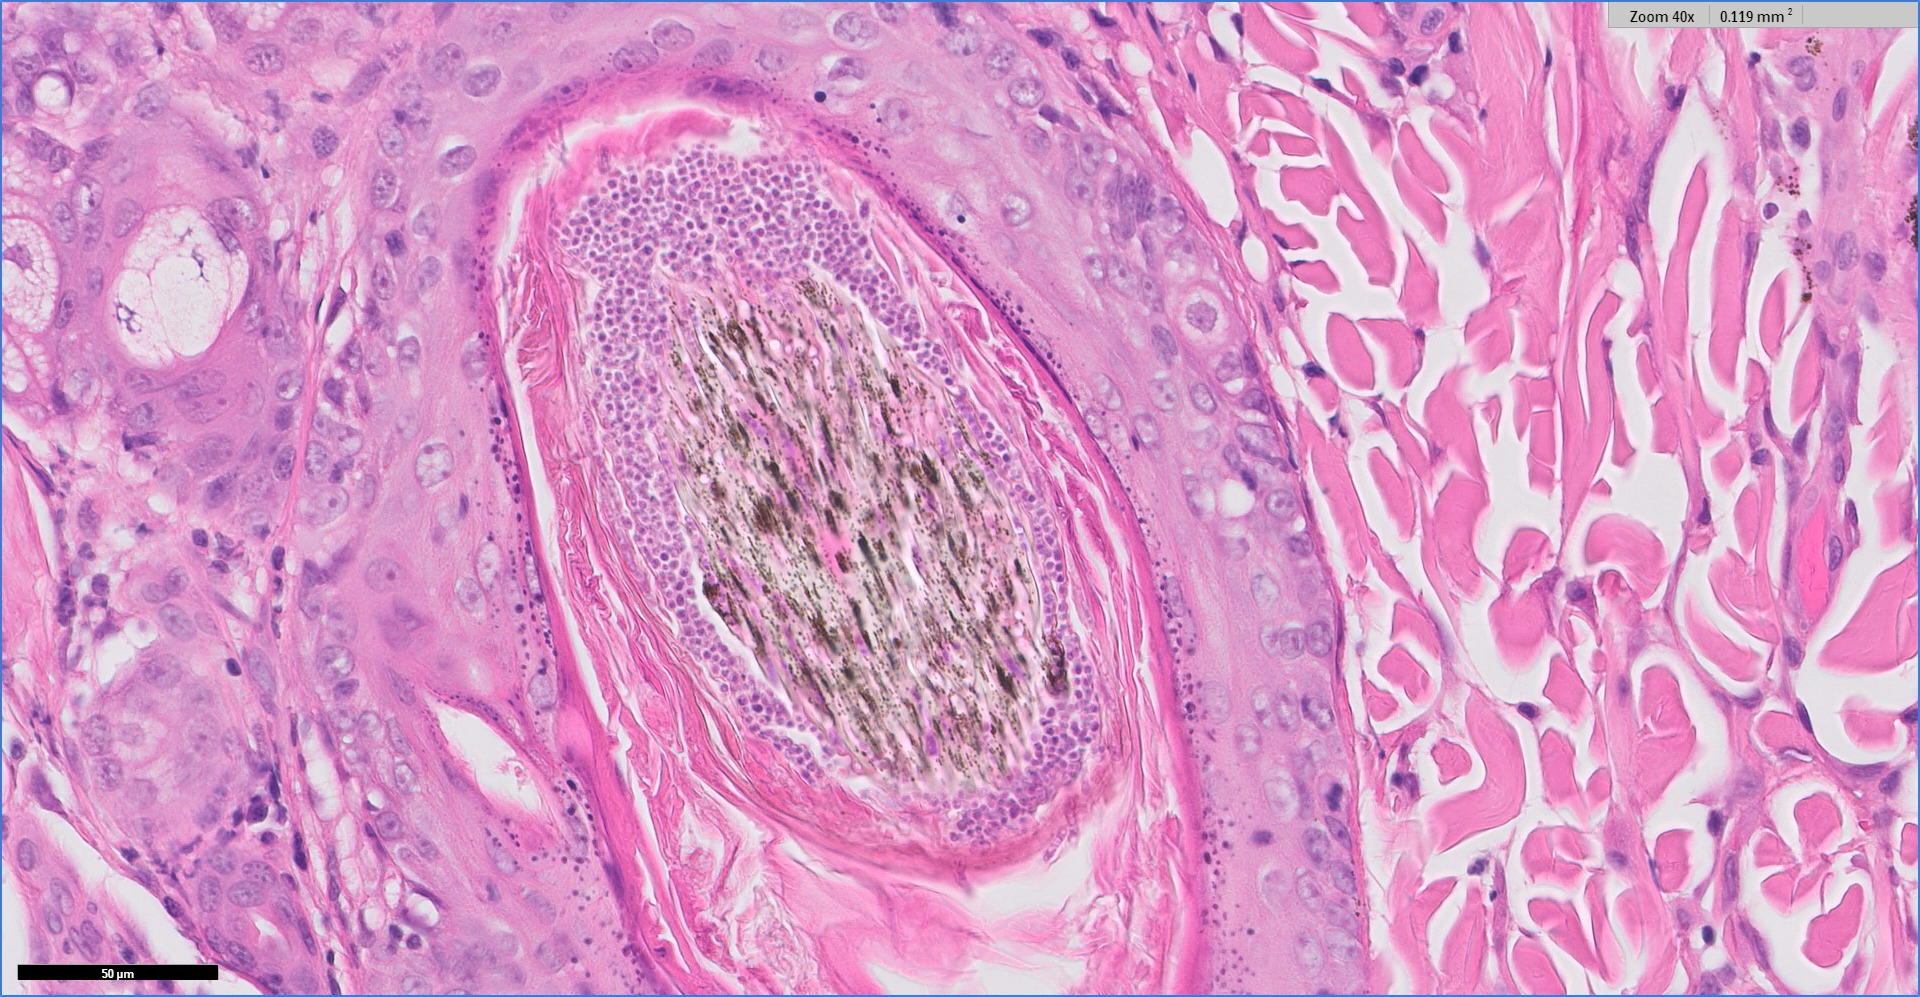

A veterinary dermatohistopathology service, VetDermPathology, to dermatologists and general practitioners who want Dr David Shearer to be part of their diagnostic team. This is not a routine general histopathology service. The service includes a second opinion / review service from previous skin biopsies supplied by dermatologists and general practitioners as well as a premium dermatopathology service for new skin biopsies via Cytopath Ltd. This is provided by Dr David Shearer BVetMed PhD CertSAD PGCertVetEd FHEA CBiol FRSB DipRCPath MRCVS. VetDermPath service details